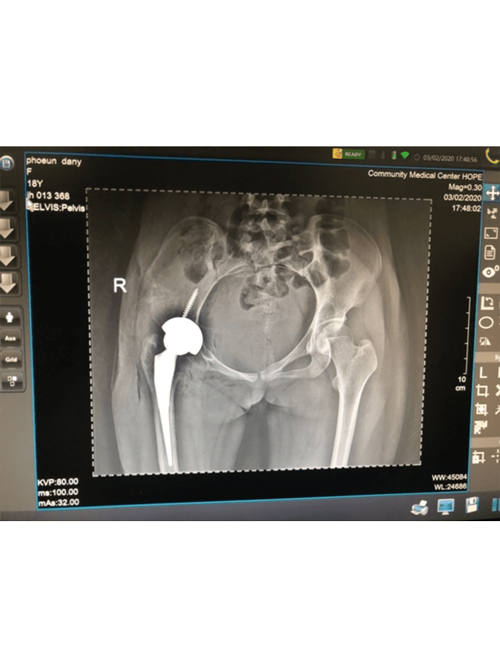

Dr. Weber and his partners participate in short term medical mission trips to Cambodia. Dr. Weber has had the pleasure of going twice now in 2018 and 2020. During these trips Dr. Weber performs total hip replacements on patients who normally would have no treatment options. To learn more and to see videos from the experience please click the links below.